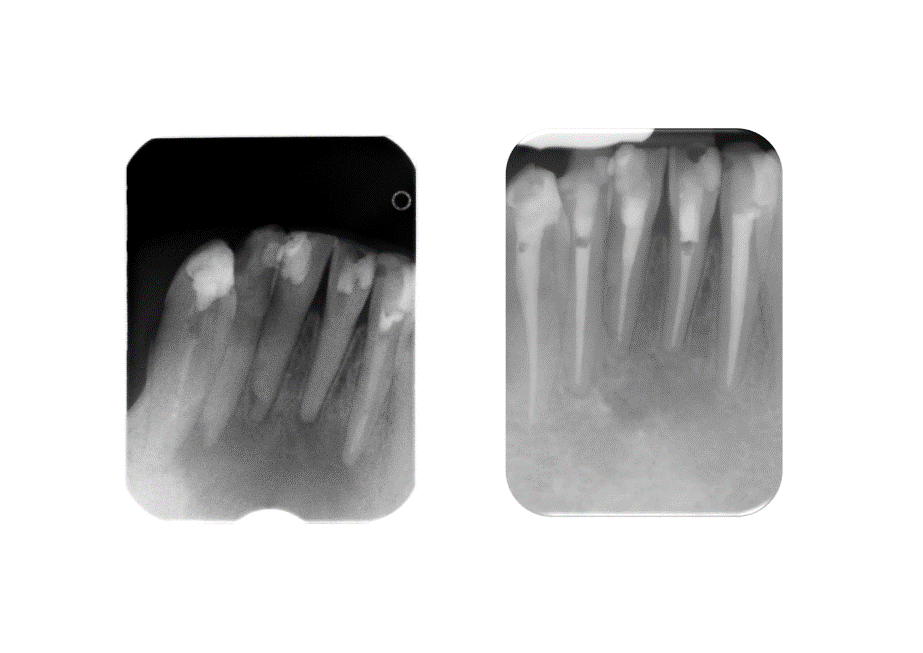

The tooth should continue to be assessed. Pic shows significant healing but still a radiolucency around the teeth – likely to be scar tissue formation but would need to be checked surgically/histologically.